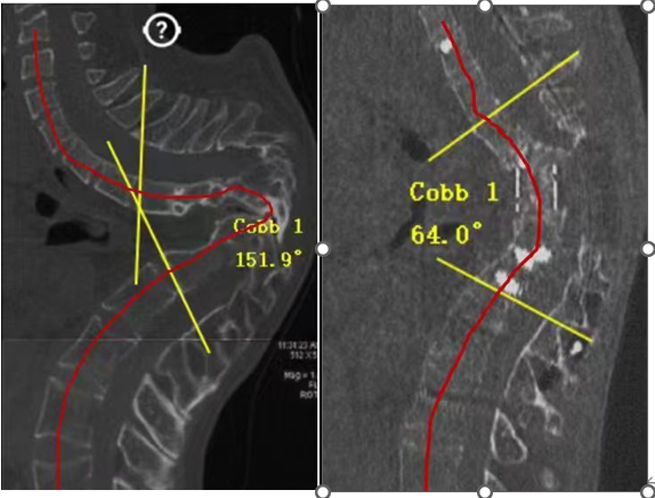

但由于患者胸椎畸形十分嚴重,影像學檢查顯示,其胸椎形變曲度已達到150°極限,手術中截癱或死亡風險極高。為有效控制手術風險,該院骨科聯合胸外科、神經外科、呼吸內科、藥劑科、營養科和護理重癥監護團隊多學科聯合會診,制定周密的手術治療方案,采用術中導航技術和全程神經電生理監測,極大提高了手術操作的精準性和安全性。

?日前,經過7小時緊張手術,黃博專家團隊為沈強完成了重度畸形脊柱的修復重建,胸椎生理曲度恢復到接近于正常的64°,解除了嚴重胸椎形變對脊髓神經進一步壓迫的風險。經過一段時間的康復治療,沈強經歷了術后感染和神經恢復等兇險的“鬼門關”后逐漸康復,重新恢復下地行走,到出院時身高還增高7厘米。